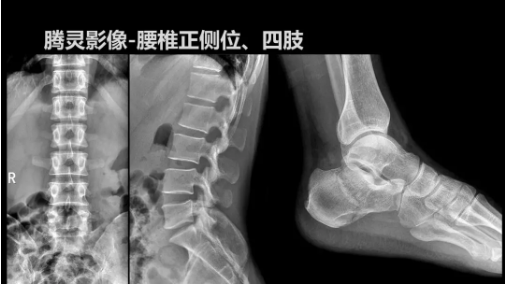

“騰靈”是安健科技的第四代動(dòng)態(tài)DR產(chǎn)品,可實(shí)現(xiàn)全科室應(yīng)用。如各類常規(guī)的X線檢查、消化道檢查、骨科檢查、婦科、兒科檢查等。此外,安健科技為“騰靈”在真正意義上實(shí)現(xiàn)多科室、多功能診斷進(jìn)行了多項(xiàng)針對(duì)性設(shè)計(jì)。